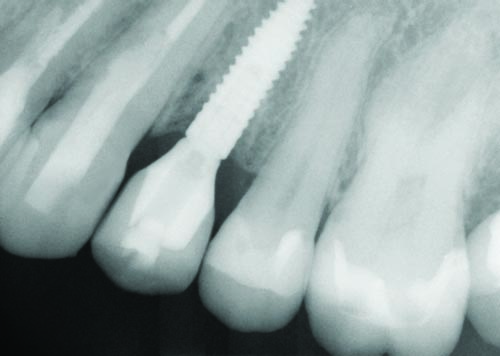

Fig. 32

Figs. 30–32: Two weeks later, the fourth appointment was reserved for restoration try-in and final impressions on the endosteal implants. It was during the fifth appointment, scheduled for two weeks later, that the implant-supported IPS E.max crown restorations were delivered, as well as the other definitive maxillary restorations, and any necessary adjustments made. These postoperative radiographs confirmed healing at the #3, #12 and #15 sites, which were all ultimately restored with Straumann implants, custom titanium abutments and IPS E.max crowns.